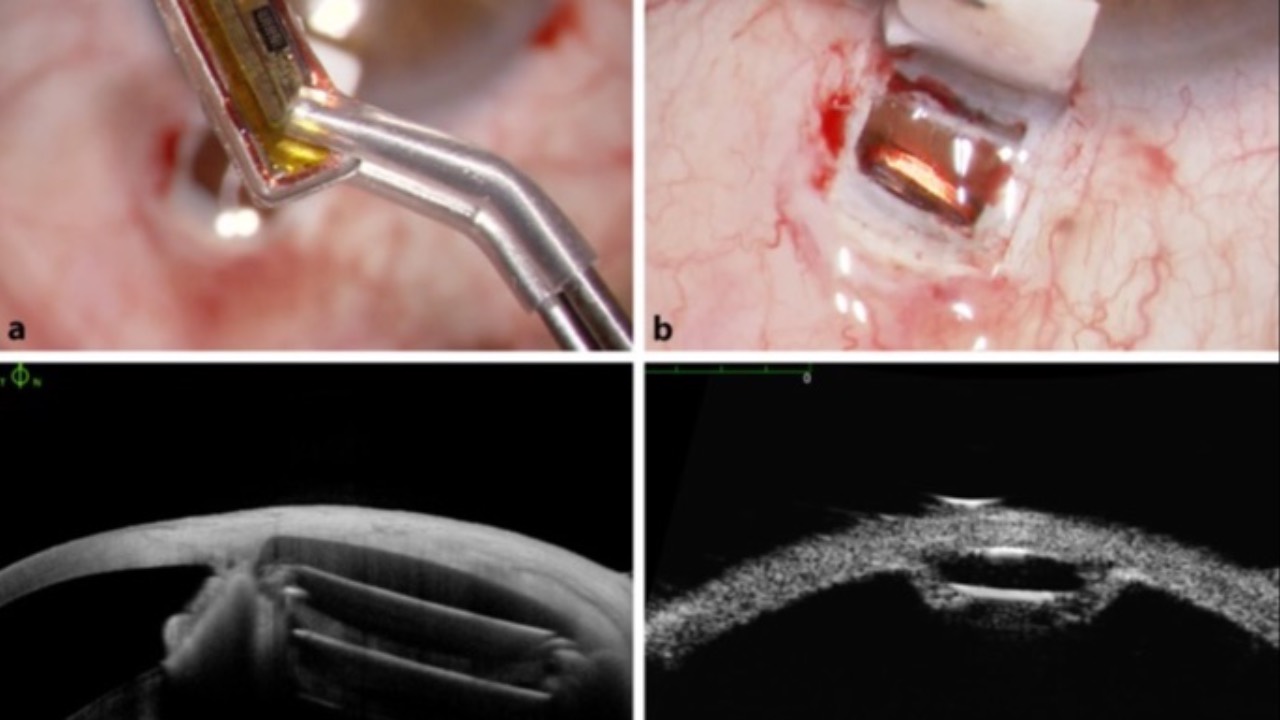

NEW COURSE! Labs & Imaging for Primary Eye Care

- Downloadable Book & Companion Course

- Modular "Go At Your Own Pace" Format

- 2 CE's & Instant Certificate